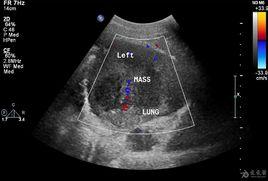

鱗狀細胞癌簡稱鱗癌,又稱表皮樣癌,常發生在身體原有鱗狀上皮覆蓋的部位,如皮膚、口腔、唇、子宮頸、陰道、食管、喉、陰*莖等處,也可發生在有鱗狀上皮化生的其...